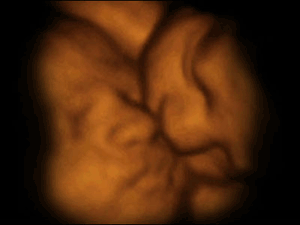

这张图见证了罕见的“双胎消失征”。图中居右的第3个胎盘是空的,这证明了多胞胎可能由于缺少营养而从子宫中消失。

双胞胎在上演“子宫中接吻”。多胞胎被认为因子宫中的互动而受益,这些互动有助于他们更快地发育。